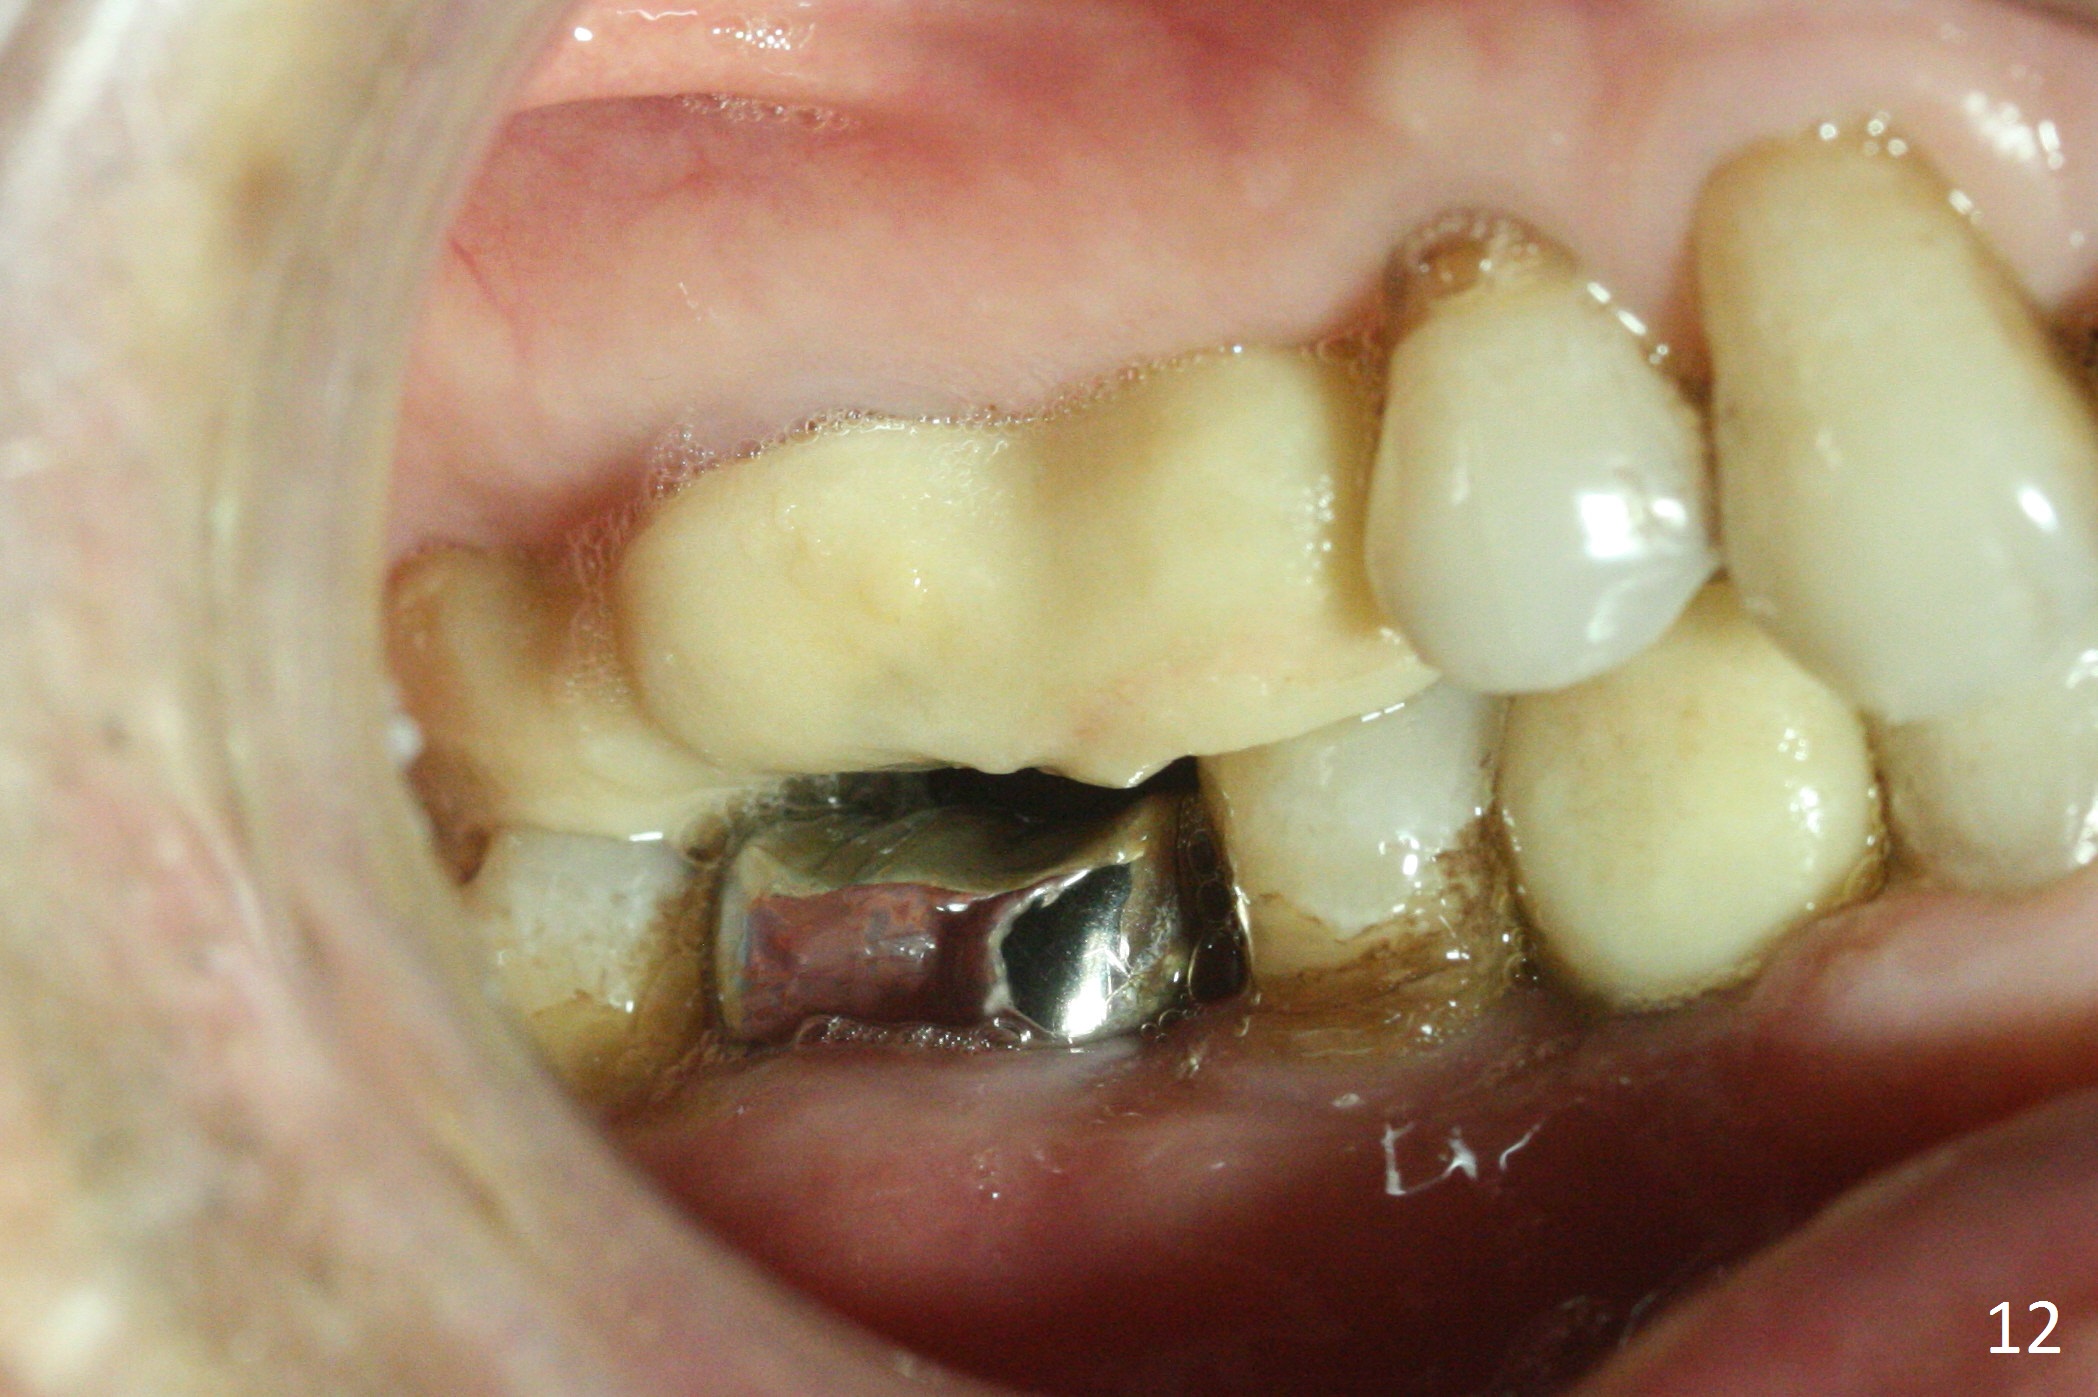

In fact the upper provisional has been extended to cover #2-4 three months postop. When the patient returns again, it is approximately 4 months postop for #2 and 4 (Fig.9,10) and 3 months for #28. Reline or make the provisional so that the teeth #5 and 29 will be intruded (Fig.11 preop pan for comparision). The tooth #30 appears to have been intruded for the past 4 months. The provisional at #3 is short so that the tooth #30 may be able to erupt (Fig.12).

Six months postop, the upper right splinted provisional between #2 and 4 is sectioned so that the tooth #3 is also free to erupt naturally (Fig.13). The patient tolerates occlusal increase well.